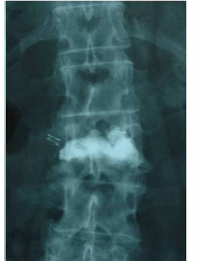

Exemple cas clínic cifoplastia

Comparació pre- i post-operatoria d’una cifopastia cementada

Dona, edat 55 anys, fractura aixafament dret de L2

Abans 1

Després 1

Abans 2

Després 2